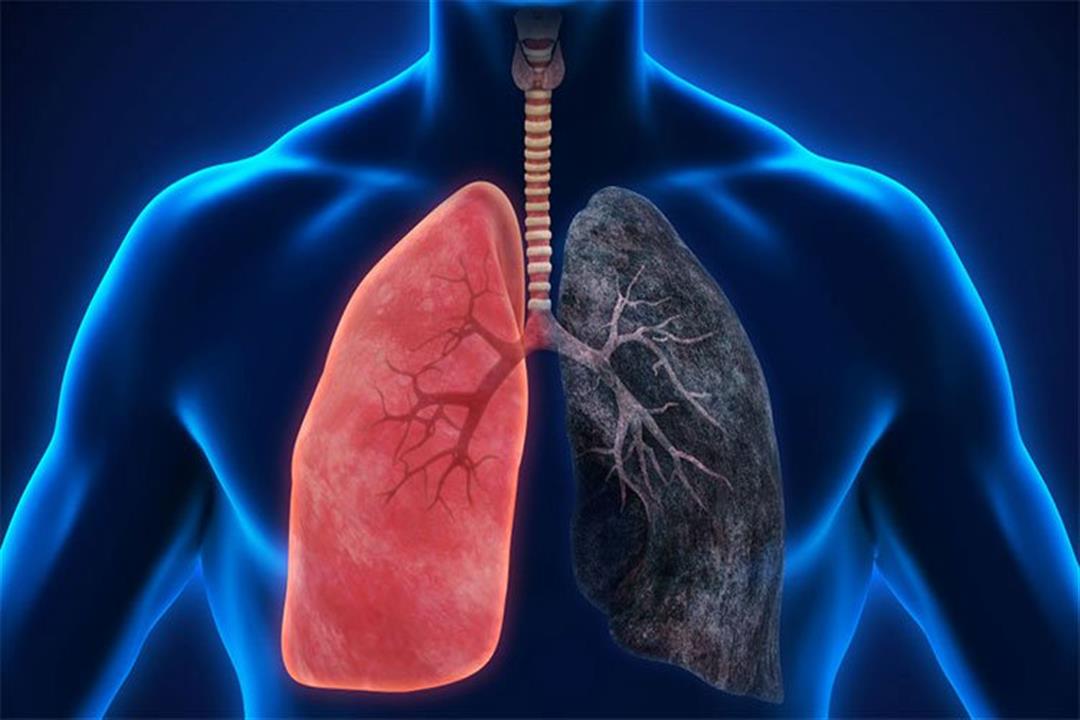

الرئة السوداء مرض صامت يسبب الإعاقة أو الوفاة اليوم السابع

التخلص من سموم الرئتين بعد الإقلاع عن التدخين صحة عرب 48

طريقة بسيطة لتنظيف الرئتين من النيكوتين البيان الصحي الأخيرة البيان

أفضل مشروب طبيعي يطه ر الرئتين من آثار التدخين قناة العالم الاخبارية